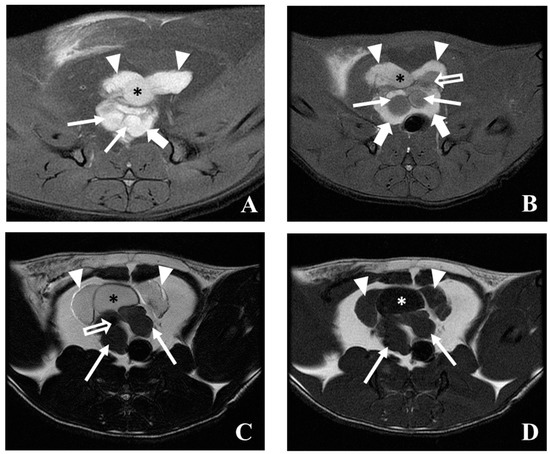

5.3. Magnetic Resonance Imaging (MRI)